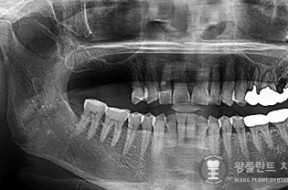

전후사례